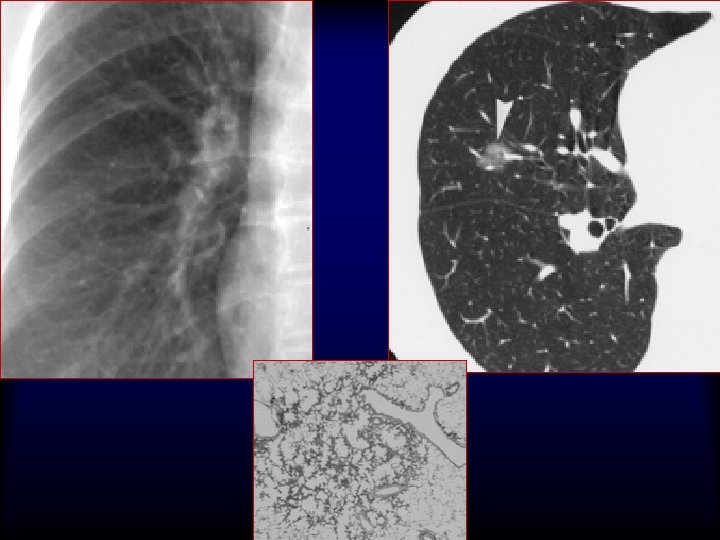

20 G/9 cm/10 T x 25 x 40 x 200 5 mm Adenocarcinoma H&E